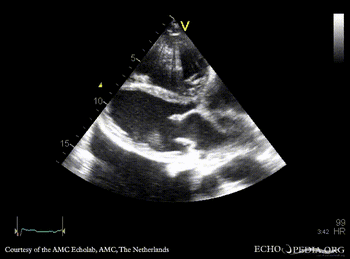

A4CH: prolaps of PMVL, enlarged left and right atrium, poor function of dilated right ventricle A4CH: Color doppler, severe mitral regurgitation